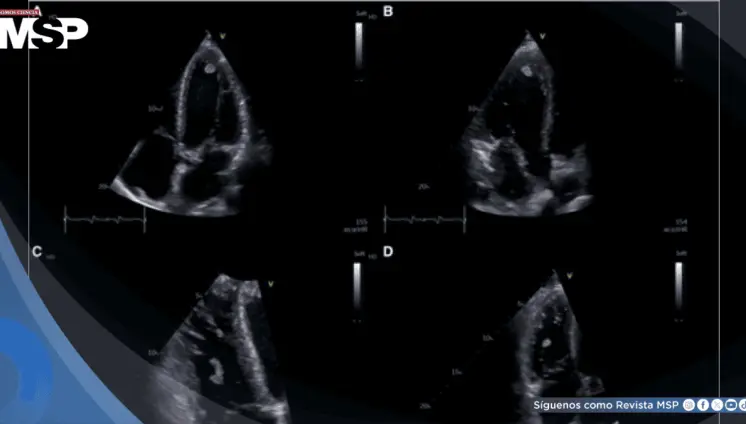

Neumonía por Mycoplasma y aleteo auricular desencadenan trombos biventriculares en paciente joven